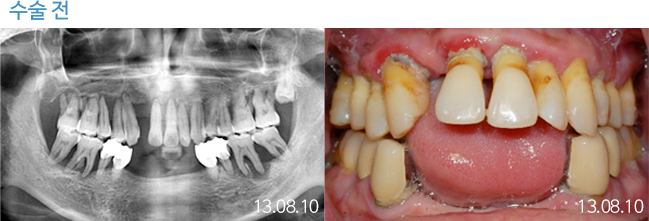

한 번 잘 심으면 10년 뒤에도 끄떡없는

더와이즈 임플란트

첨단 장비를 이용한 정확한 진단, 안정성이 입증된 정품 재료 사용,

노하우가 풍부한 숙련된 의료진의 시술 등이 임플란트 수명을 결정합니다.

※ 실제 본원에서 치료 받은 환자의 동의를 얻어 게재했습니다.

개인의 특성에 따라 부작용이 발생할 수 있으므로 담당의와 충분히 상의하시길 바랍니다.